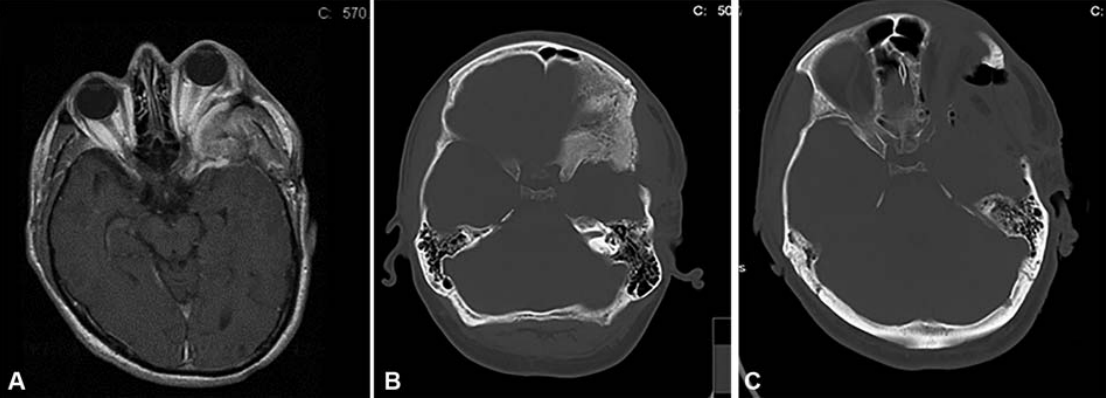

Cavernous sinus meningioma (CSM) with orbital involvement presents a unique challenge to modern-day neurosurgeons. In the modern era of preventive medicine with enhanced screening tools, physicians encounter CSM more frequently. An indolent natural history, late clinical presentation, close proximity to vital neurovascular structures, poor tumor-to-normal tissue interface, and high risk of iatrogenic morbidity and mortality with aggressive resection add to the complexity of decision-making and optimal management of these lesions. The clinical dilemma of deciding whether to observe or intervene first for asymptomatic lesions remains an enigma in current practice. The concepts of management for CSM with orbital involvement have gradually evolved from radical resection to a more conservative surgical approach with maximal safe resection, with the specific goals of preserving function and reducing proptosis. This change in surgical attitude has enabled better long-term functional outcomes with conservative approaches as compared with functionally disabled outcomes resulting from the pursuit of anatomical cure from disease with radical resection. The advent of stereotactic radiosurgery as an adjunct tool to treat residual CSM has greatly shaped our resection principles and planning. Interdisciplinary collaboration for multimodality management is key to successful management of these difficult to treat lesions and tailor management as per individual's requirement.

海绵窦脑膜瘤(CSM)是较常见的原发性海绵窦病变。位于CS的肿瘤占全部颅内肿瘤的1%,其中41%为CSM。这些病变较常见于三四十岁的女性。CSM通常累及超出CS本身的蝶眶区域,可能导致视力下降和眼球突出,由于直接压迫或骨质增生的继发影响。CS被描述为一个解剖上的宝石盒,隐藏在中颅窝的颞叶下,从眶上裂(SOF)的前上方延伸到后下方的Meckel洞穴。我们目前对复杂的CS外科解剖结构的理解以及对CS的新颅底方法的开发,都源于神经外科视觉学家的提出性工作,如帕金森、拉姆齐、塔普塔斯、哈库巴、多伦克、乌曼斯基和卡瓦塞。CSM的治疗方案包括单纯的观察、放射线和手术或上述几种方法的组合,取决于患者的年龄、一般情况、症状学和肿瘤大小。本专题综述讨论了眼眶受累的CSM的自然病史、治疗算法、适应症和治疗目标以及手术方法,特别强调多模式管理和跨学科协作。